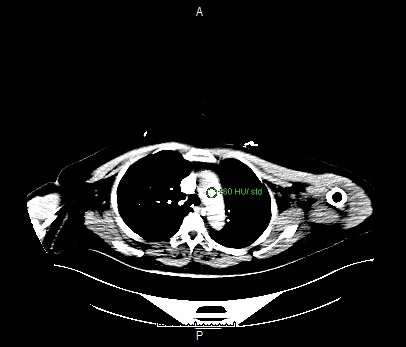

Monitoring

- Single click on the pre-monitoring image

- Single click again to activate purple circle for triggering

- Drag and drop the circle inside the aortic arch region

- Click TRIGGERING tab

- Set the Hounsfield Unit value to 80

Setting the ROI circle for triggering

Contrast triggering start